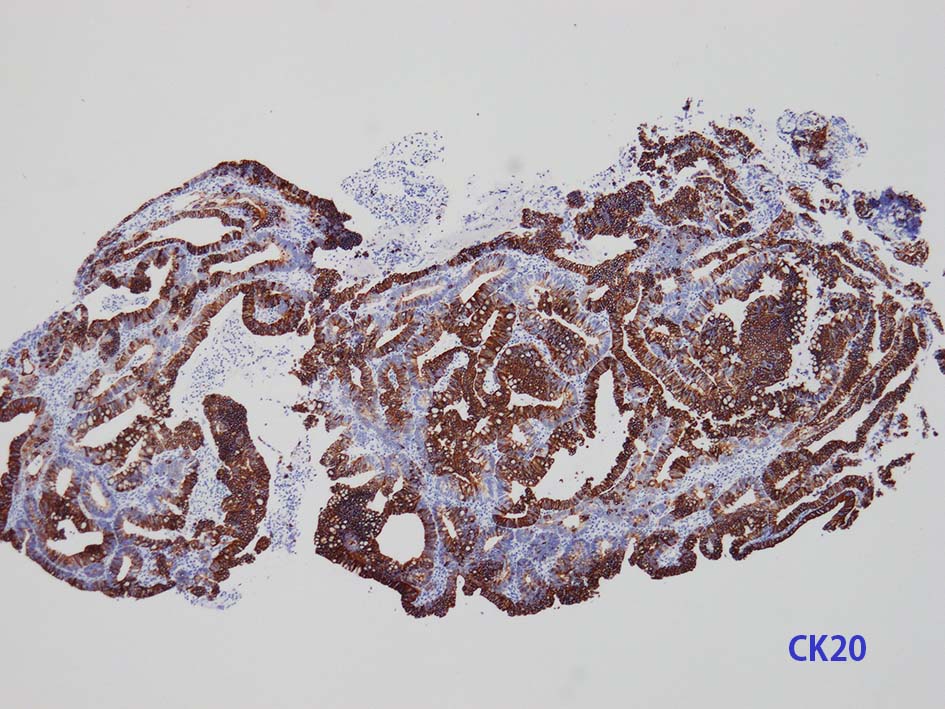

膀胱原発腺癌の診断に, サイトケラチン7および20、34βE12、トロンボモジュリン、CDX2およびβカテニンなどの免疫組織化学的パネルが提案されている。しかし他の原発部位に発生する腺癌と組織像だけでなく免疫組織化学的特徴が重複している. 原発性腺癌と転移性腺癌では予後や治療法が大きく異なるため, 鑑別診断において膀胱腺癌の診断を下す際には、臨床的、画像的、組織的、および免疫組織化学的な相関を注意深く確認する必要がある。

mark-g.gif 免疫染色